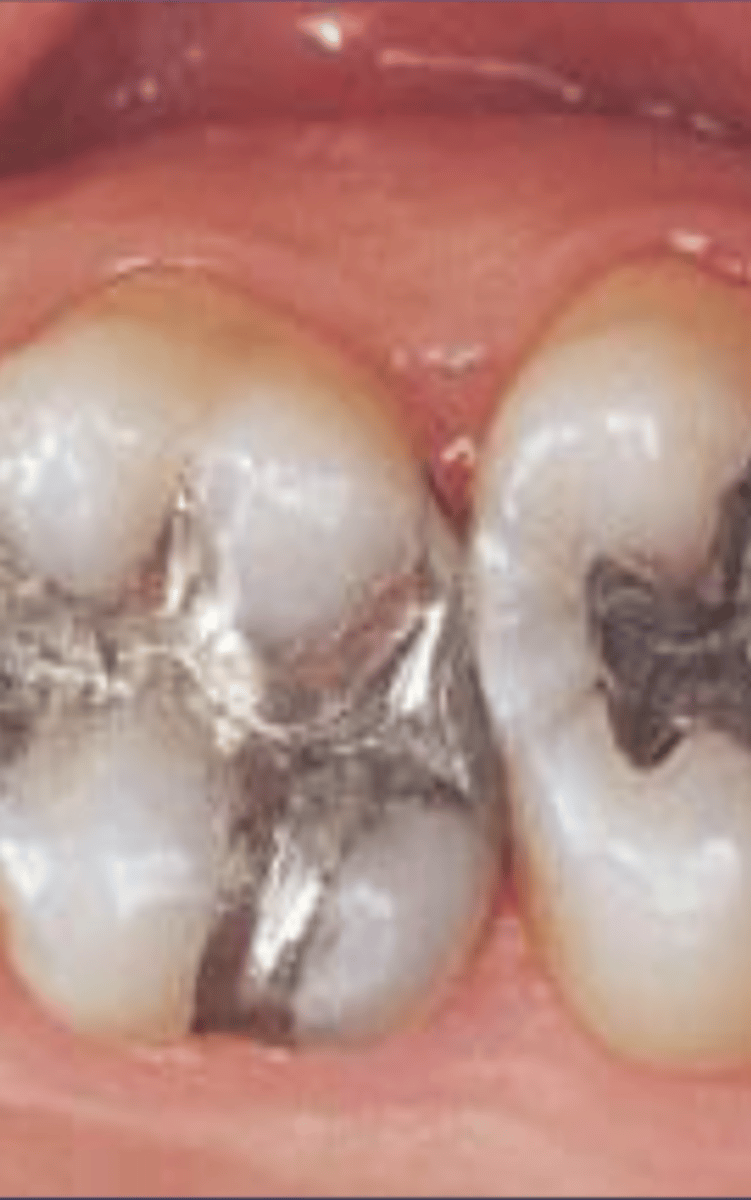

Amalgam restorations

Completely opaque

- One surface amalgam - B,L,O, I

- Multisurface - MO, MOD, ML, OL

Amalgam examples